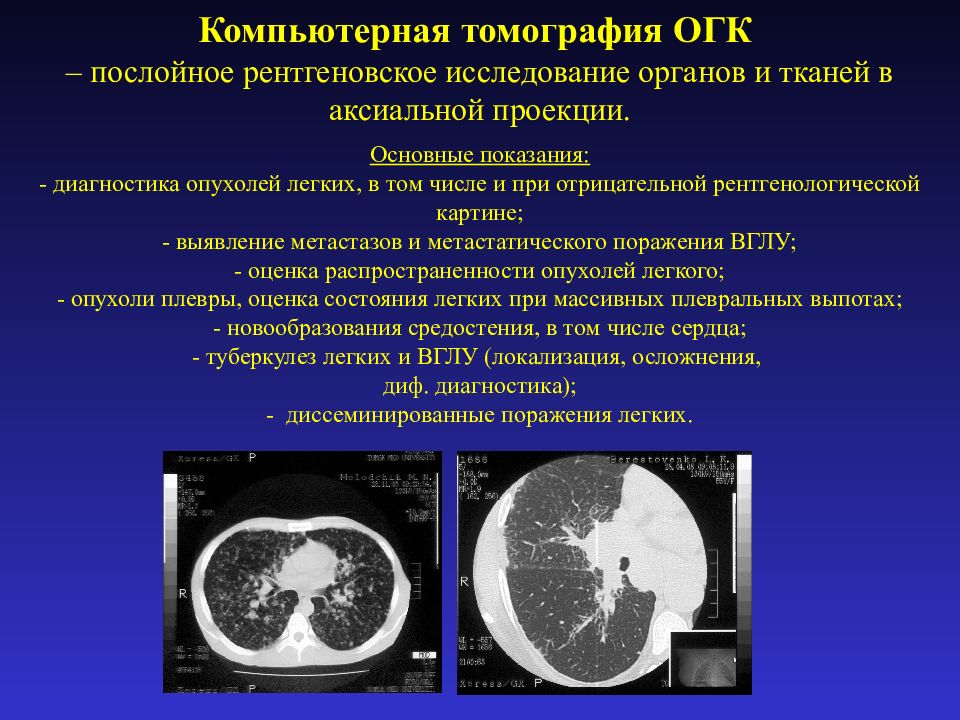

Рентгеновские и МРТ снимки легких